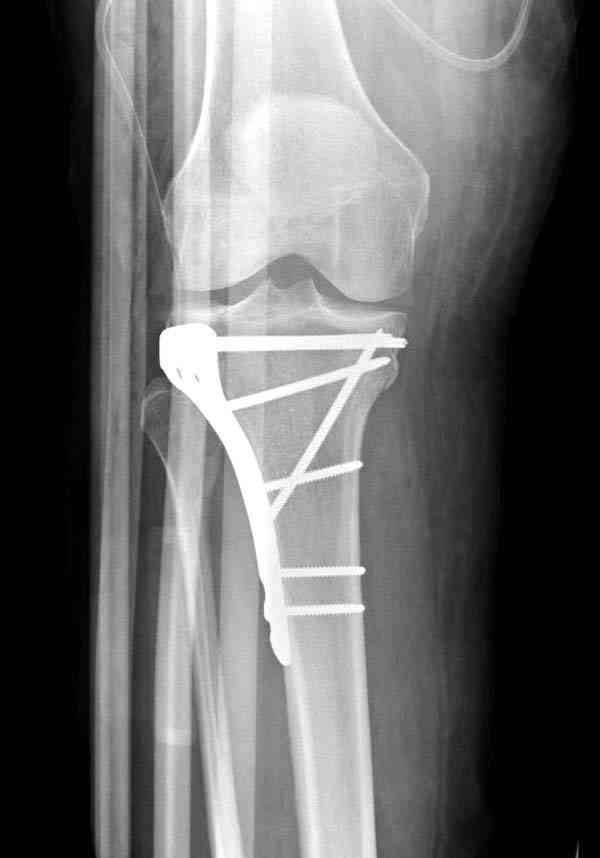

центральная импрессия, а при ипрессии с краевым переломом - после приподнимания импрессии опорная (Butress) пластина, как на снимке.